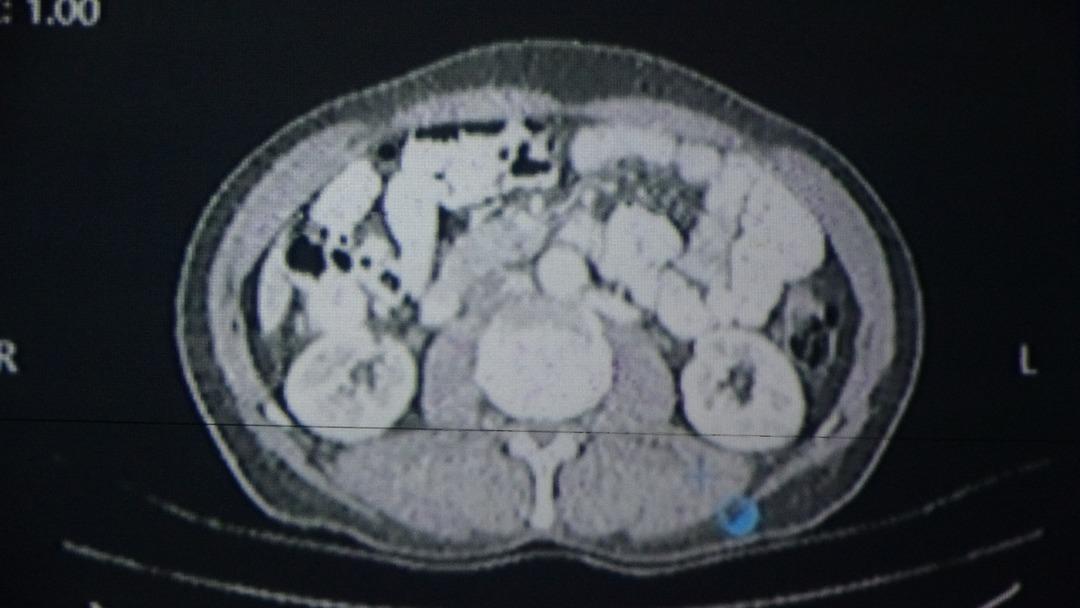

Çalışmada örnek vakalardan biri olarak, Ericiş bölgesinde yaşayan 56 yıllık Sabri SaruylediZ değerlendirildi. Yapay zeka tarafından desteklenen yazılım tarafından önerilen tedavi planı, doktorların kararlarıyla uygulanmıştır. Sarıyız, bu yol sayesinde başarılı cerrahi operasyon sağlığı kazandı.

Sabri Sarıyiz, “Önce kemoterapi ve radyoterapi gördüm. Yiyecekte bir kitle vardı. Öğretmenimize başvurduğum genel cerrahi uzmanı Prof. Dr. Sebahattin Celik.